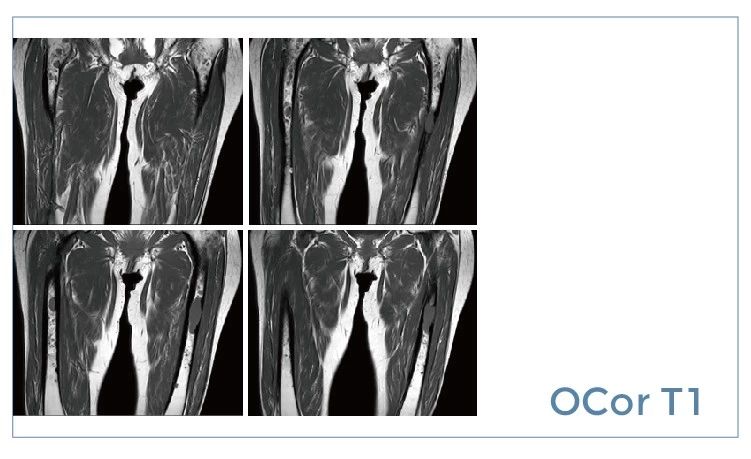

【朗润影像档案】磁共振影像病例分享(编号20190712)